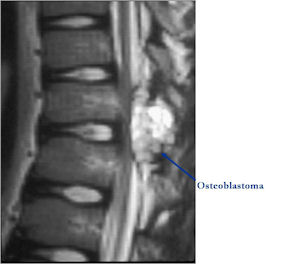

MRI:

- Also useful in determining extent

- There is often extensive edema around the tumor in the surrounding bone and soft tissues that can lead to a misdiagnosis of a malignant tumor.

- Spine (40% of cases; usually posterior elements)

Osteoblastoma